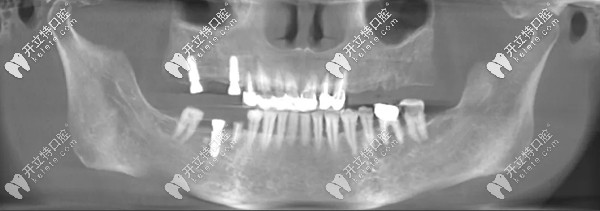

王阿姨多顆牙缺失(右下1顆、右上2顆),她說之前牙齒做過治療后就出現(xiàn)掉牙現(xiàn)象,每次咀嚼稍微堅(jiān)硬的食物牙齦就會生疼;

王阿姨種牙前

▲王阿姨種牙前牙片

王阿姨種牙后

▲王阿姨種牙后牙片